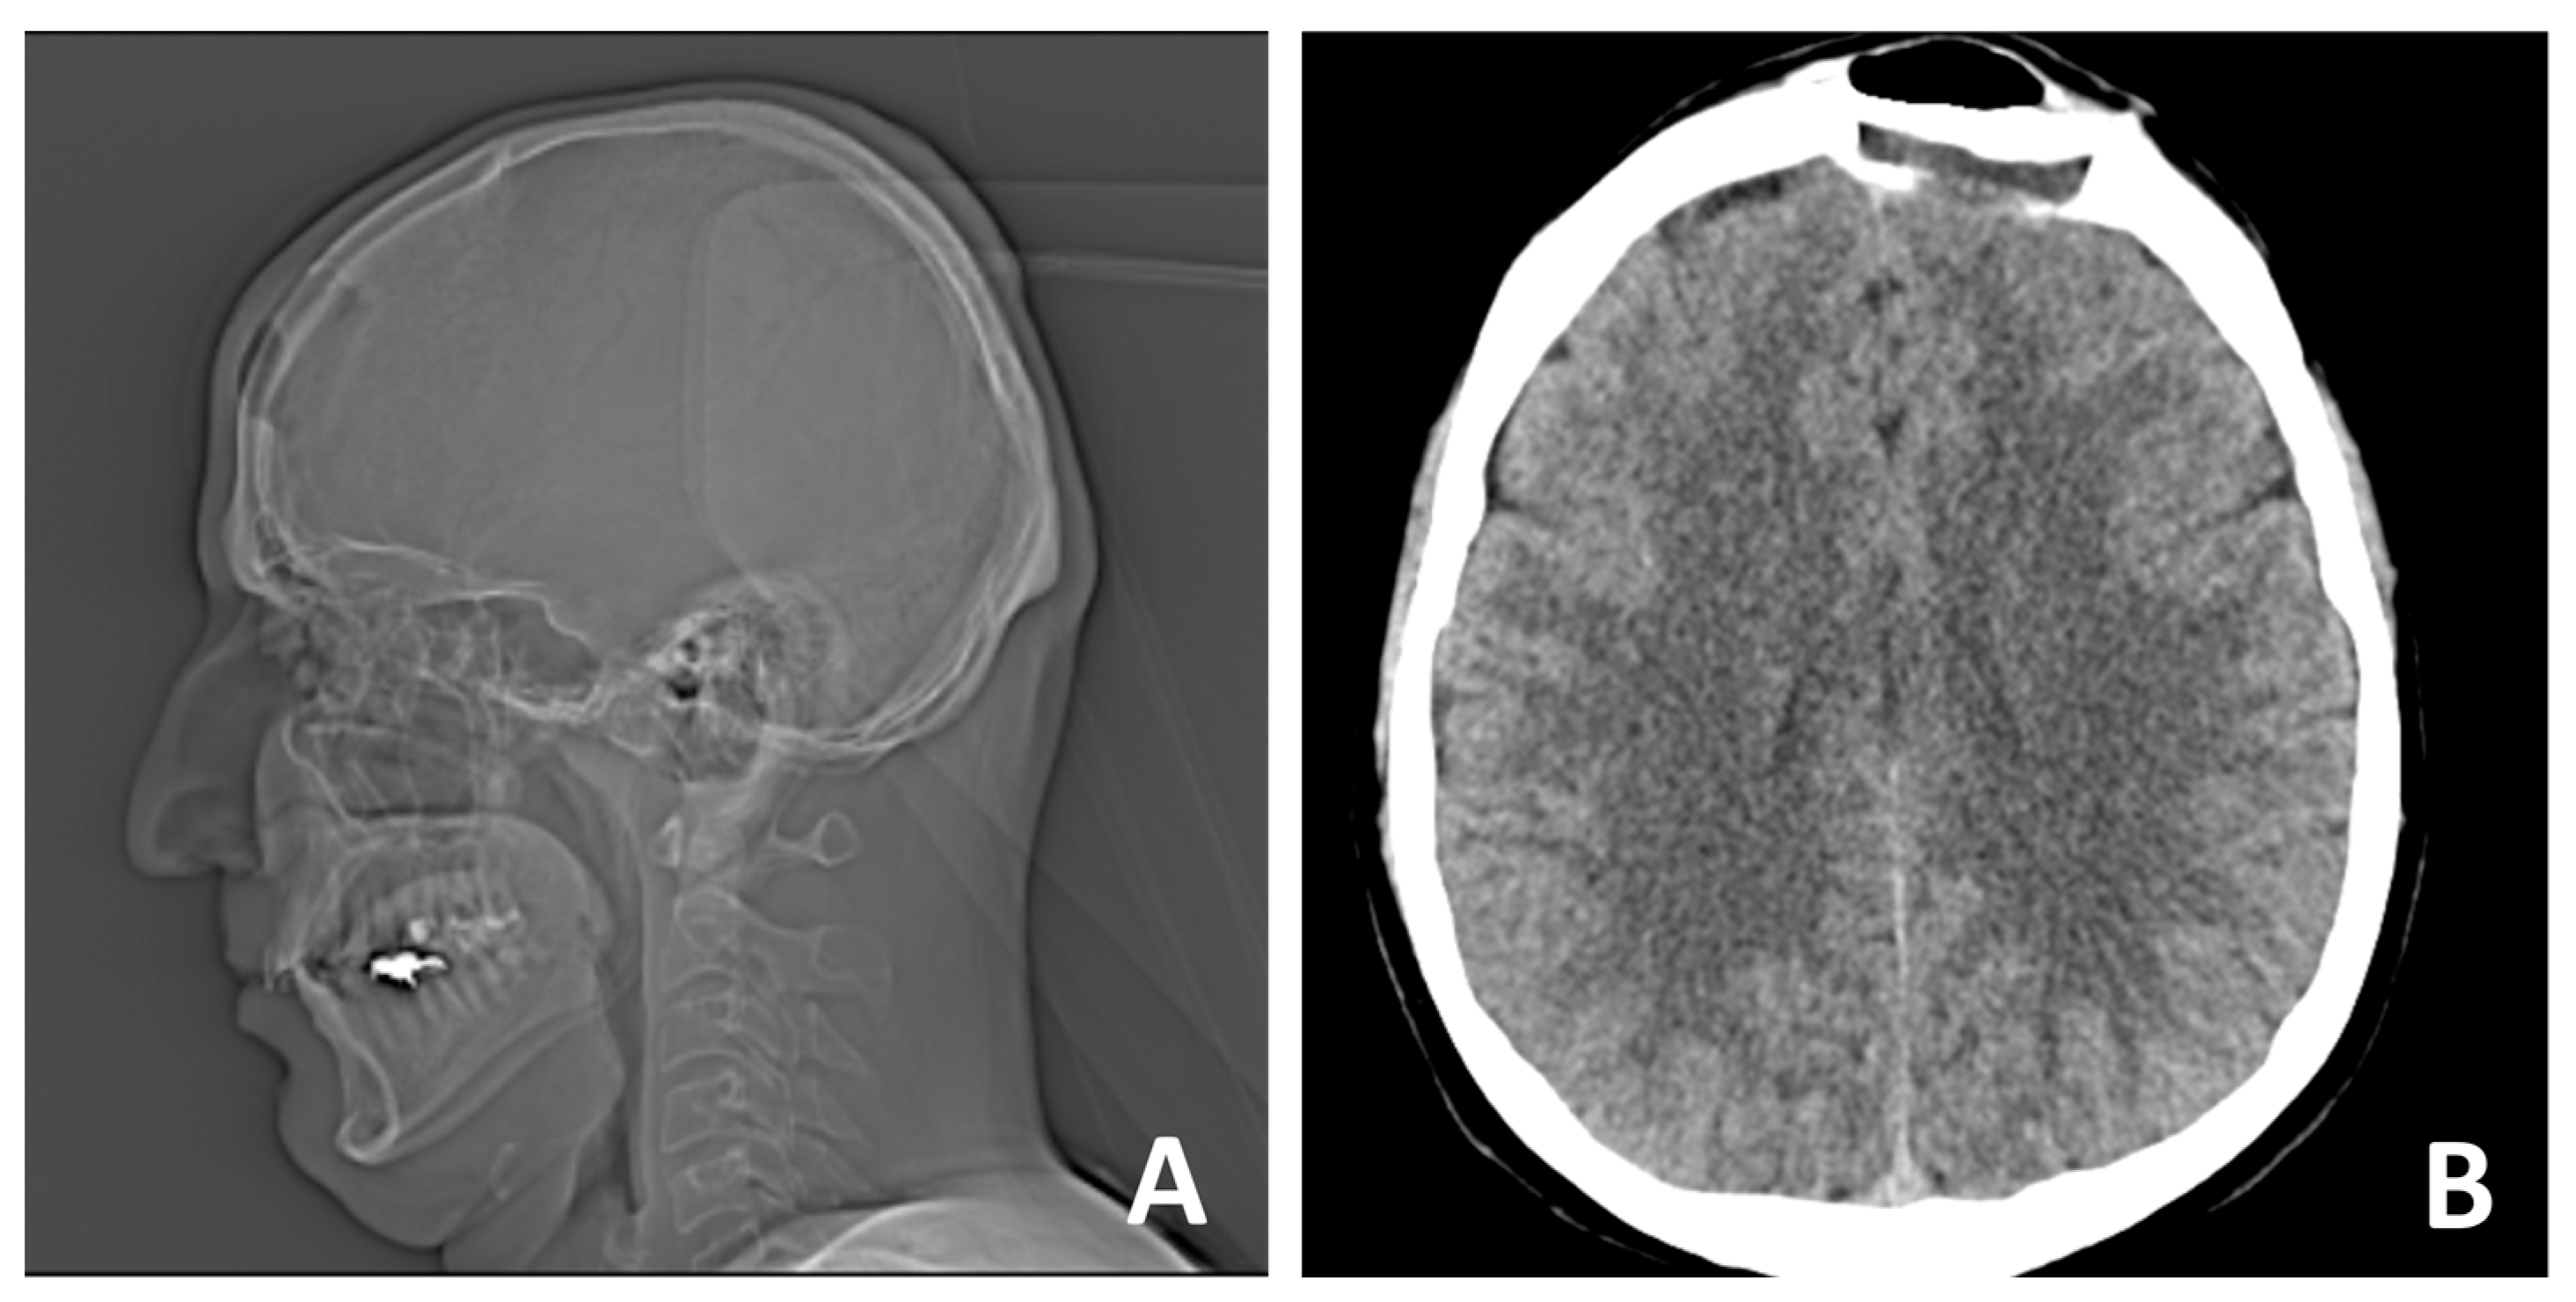

2. Case Report

- Autologous iliac crest bone grafts offer robust cortical and cancellous components suitable for reconstructing moderate to large cranial defects and remain the gold standard for calvarial reconstruction due to their osteoconductive, osteoinductive, and osteogenic properties. Despite potential donor-site morbidity, including pain, gait disturbance, hematoma, or sensory disturbance, the iliac crest remains a favored source due to its accessibility and structural quality [28,29,30]. In our case, the bone graft was successfully harvested and contoured to match the frontal defect and was secured with vicryl suture, achieving a stable reconstruction and satisfactory aesthetic outcome. Especially in the frontal region, calvarial grafts and iliac crest grafts yield excellent contour match and longevity.